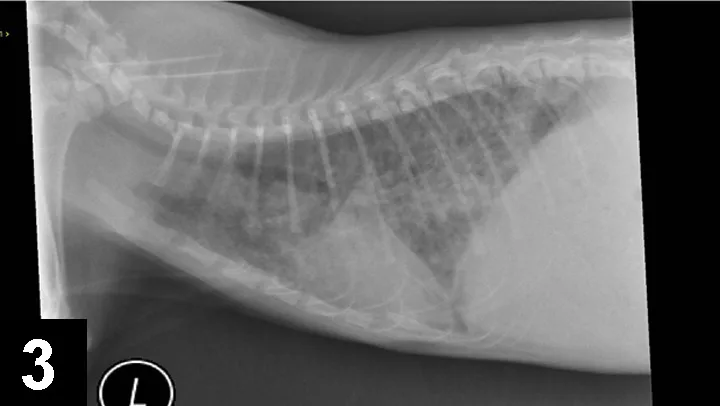

Radiographic findings consistent with airway disease include donuts and tram lines, which are supportive of bronchial thickening and hyper­inflation from expiratory flow limitation. Some cats with lower airway disease also have a collapsed middle lung lobe (Figure 2).

Figure 2. Cat with collapsed middle lung lobe (arrow) in addition to lower airway disease.